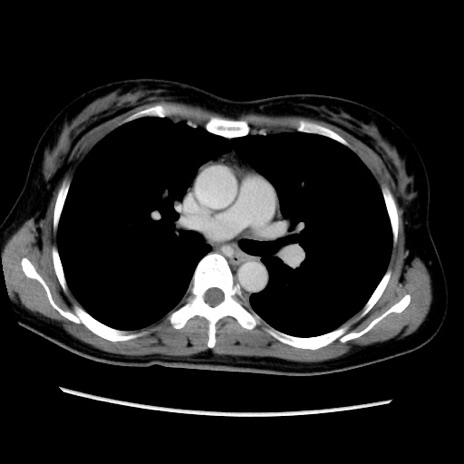

症例39(横断像)

【症例】40歳代女性

【主訴】上下腹部痛

【現病歴】2日目から下腹部痛あり。夜間は痛みで眠れなかった。昨日より上腹部痛と下痢が出現。臥位で痛みは軽快したため、休んでいた。本日になって臥位でも立位でも痛みが強くなってきたため救急要請。

【既往歴】子宮内膜症

【身体所見】部:平坦・軟、左上下腹部に圧痛あり、反跳痛あり。

【データ】WBC 21800、CRP 26.78